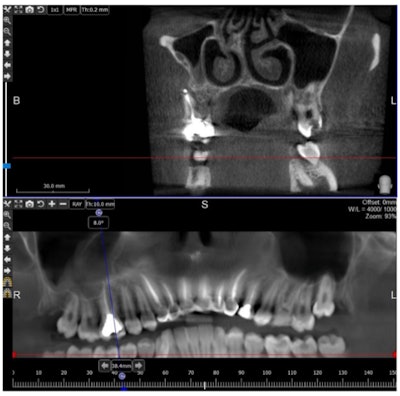

She underwent a cone-beam computed tomography scan that confirmed a bony defect at the apex of the mesiobuccal root of the upper first molar, where the continuity of the buccal plate was impaired, the authors wrote.

A cone-beam computed tomography scan showing a bony defect at the apex of mesiobuccal root of the upper first molar.